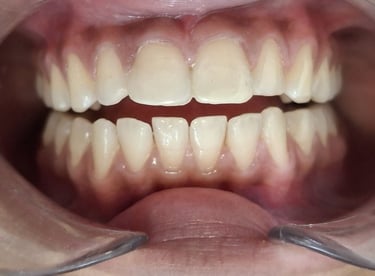

Professional Teeth Cleaning in Shyamal, Ahmedabad

Gentle, properly performed and tailored teeth cleaning for each person giving you comfort, safety and visible results. People from Shyamal and nearby areas of Ahmedabad visit our clinic for comfortable and very effective teeth cleaning.

After

All images shown here are real teeth cleaning cases treated at our clinic with patient consent.

Professional teeth cleaning helps remove plaque, tarter, and surface stains that regular at home brushing can not.

At Shree Dental Care, teeth cleaning is performed gently with focus on patient experience, comfort and long term oral health.